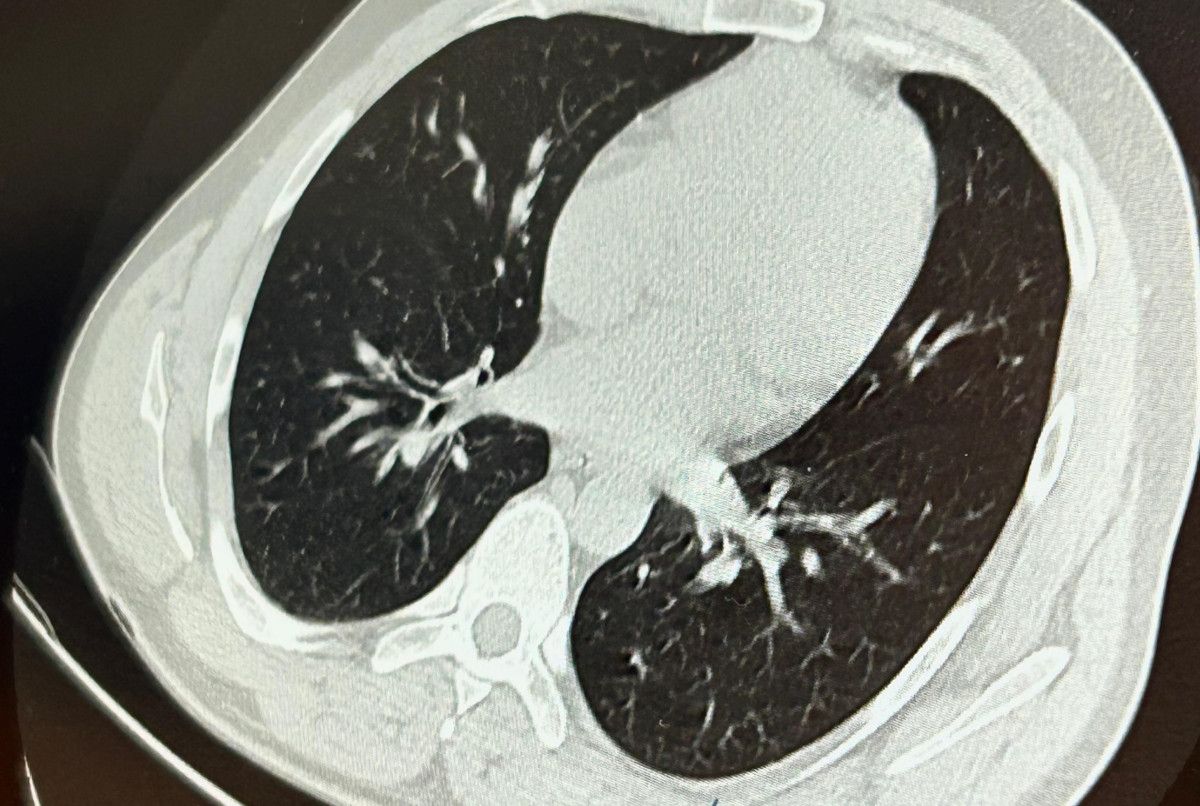

Bunun üzerine toraks ve batın BT (bilgisayarlı tomografi) görüntülemesi istedik. Sonuçlarda implantın akciğerden çıktığı ve vücutta herhangi bir yerde bulunmadığı tespit edildi" diye konuştu.